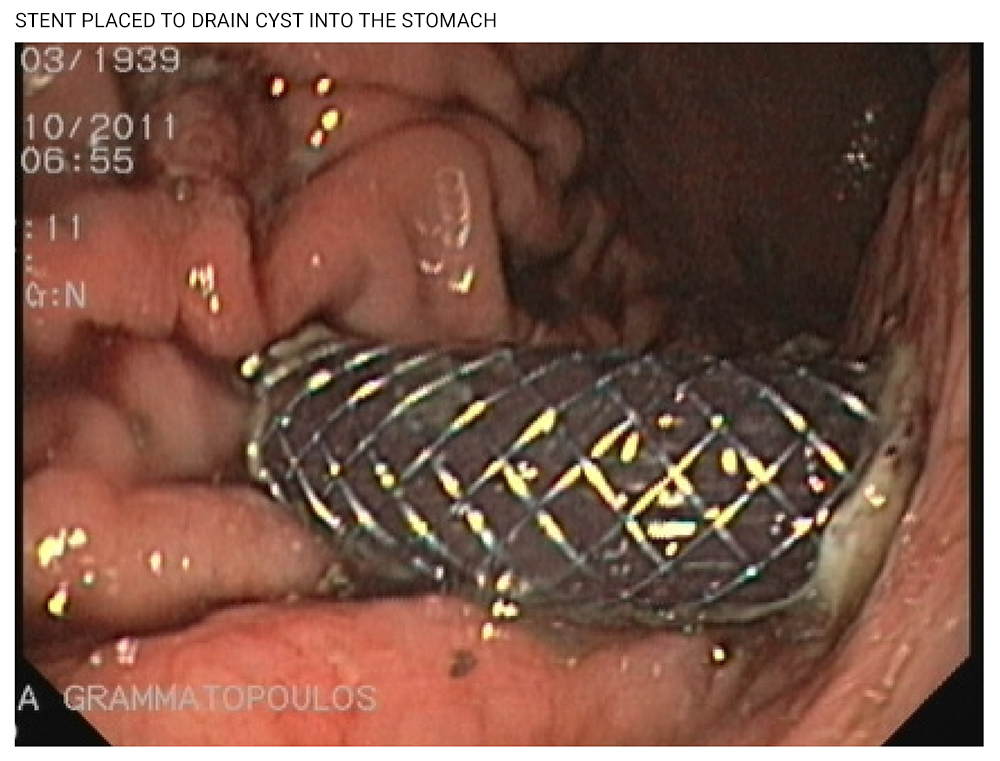

Pancreatic Pseudocyst Drainage

Pseudocysts make up 75% of cystic pancreatic lesions. They are localized collections of fluid rich in pancreatic enzymes found around the pancreas. These collections are separated from a fibrous and granulation tissue wall. Pseudocysts are created following pancreatitis or injury that causes damage to the pancreatic duct and leakage of pancreatic fluid to the omental bursa.

In the last few years, pseudocysts are treated endoscopically. The cyst is detected through endoscopic ultrasound. A tunnel is created between the stomach and the cyst and a special metal stent is then placed in the area. This way, the contents of the cyst drain into the stomach. The procedure is practically bloodless and patients are discharged in 24 hours, having avoided a surgical procedure that would have kept them in bed for days.

Conclusions:

This endoscopic method is performed at Metropolitan Hospital. It is safe and painless, with very low hospitalization costs.